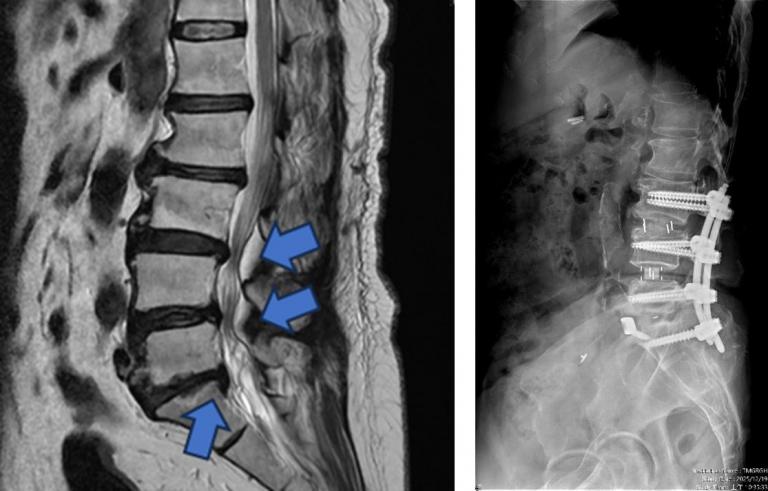

▲【手術前及手術後】手術前有脊椎滑脫不穩定及脊椎狹窄造成神經壓迫(左圖),手術後除了重建椎間高度,也將腰椎的生理曲線重建為較理想的前凸狀態(右圖)。(圖╱台中市醫提供)

一名65歲婦人長期飽受腰痛、下肢痠麻及坐骨神經痛困擾,行走距離逐年縮短,嚴重影響日常生活。過去曾接受膝關節保膝手術及脊椎內視鏡減壓治療,初期恢復良好,但因仍存在多節段腰椎退化性狹窄與骨刺問題,加上彎腰負重與久坐習慣未能完全改善,症狀逐漸惡化,甚至出現神經性跛行。經臺中市立老人復健綜合醫院骨科部副部長林琮凱醫師詳細檢查後,診斷為第三、四、五腰椎合併第一薦椎多節段脊椎狹窄與神經壓迫。醫療團隊與病患及家屬充分溝通後,決定採用電腦導航輔助之前位/前側位脊椎融合手術,合併後方骨釘固定,一次完成多節段重建。術後病患神經症狀明顯改善,恢復行走能力,生活品質大幅提升。

相較於傳統脊椎手術需分部位分階段進行、住院與復原時間長,中醫大市醫引進的前位或前側位脊椎融合手術,搭配 3D 電腦導航系統,可在同一次手術中完成多節段融合與多部位重建。手術採間接減壓方式,不需直接進入脊椎腔,大幅降低神經損傷風險。多數病患可於手術當日或隔日配戴背架下床行走,疼痛較少、恢復期明顯縮短,同時提升醫療效能與病患滿意度。